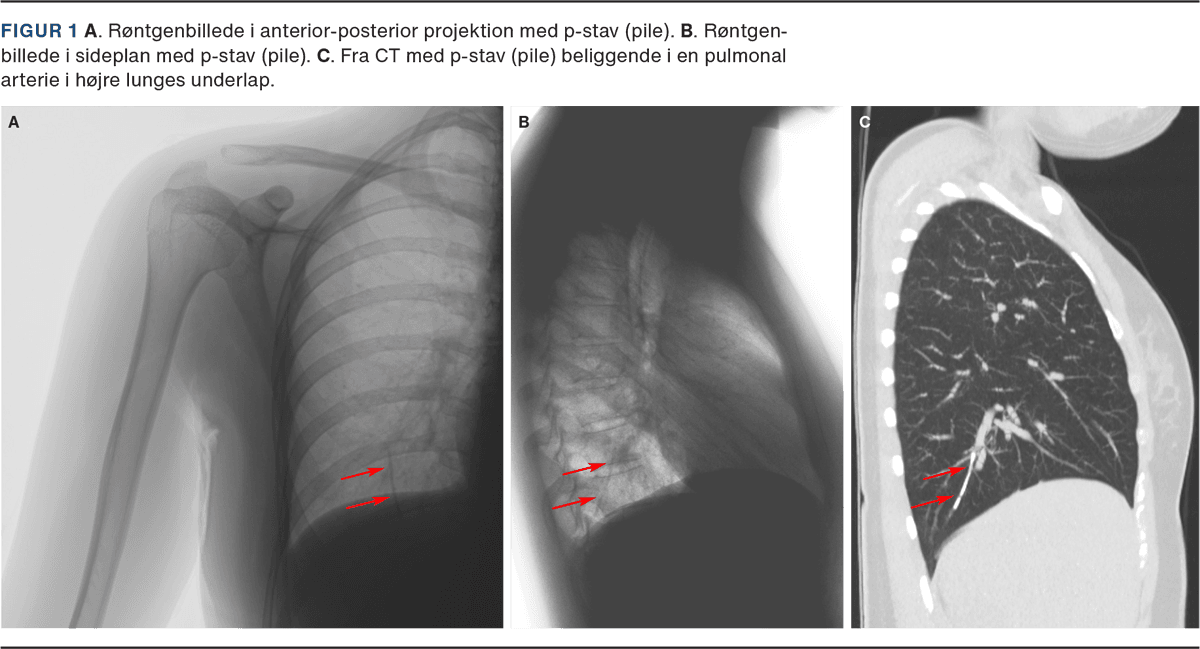

En ung kvinde henvendte sig i ambulatoriet på et regionssygehus i Grønland til rutinemæssigt skift af p-stav. P-staven var blevet anlagt ukompliceret i højre overarm tre år forinden. Patienten vejede 42 kg og havde et BMI på 18 kg/m2 året før anlæggelsen. Et mindre ar ved indstiksstedet blev lokaliseret på indersiden af patientens højre overarm, men p-staven kunne ikke palperes under huden. Hele patientens overarm blev skannet med ultralyd, men det lykkedes ikke at lokalisere p-staven. På mistanke om, at p-staven var vandret, fik patienten foretaget et røntgenbillede af højre overarm og højre thoraxhalvdel i anteriort-posteriort plan (Figur 1A). Her blev et lineært fremmedlegeme af dimensionerne 40 × 2 mm svarende til en p-stav lokaliseret. Da røntgenbillederne kun var taget i ét plan, kunne den præcise anatomiske placering af fremmedlegemet ikke vurderes. Det blev først antaget, at p-staven var vandret i det subkutane rum og nu lå i subcutis nær brystet. Derfor blev der foretaget et røntgenbillede i sideplan, og her sås et fremmedlegeme i højre lunges underlap (Figur 1B).

På regionssygehuset var røntgenundersøgelser og UL-skanning de eneste billeddiagnostiske muligheder, og patienten blev henvist til Dronning Ingrids Hospital i Nuuk, hvor p-stavens beliggenhed i en mindre pulmonal arterie i højre lunges underlap blev bekræftet med CT (Figur 1C). Der var ingen tegn på blødning eller lokale reaktive forandringer.